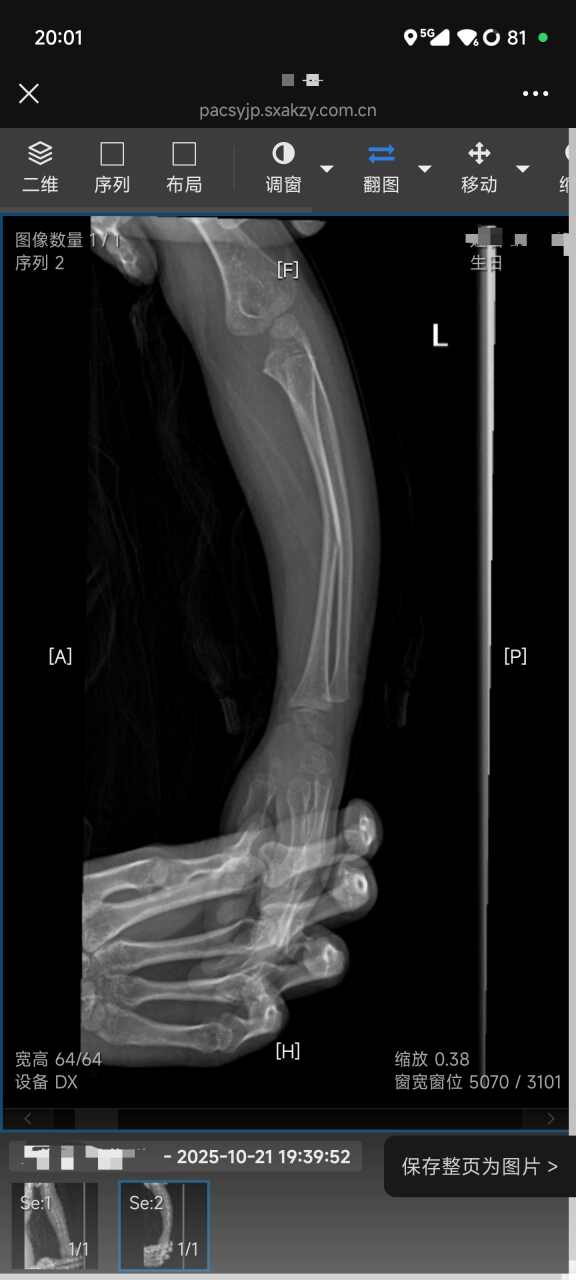

我要投诉安康爱酷少儿体能中心(金州广场店):我4岁的孩子于2025年10月21日晚7点在该中心参加体能训练课时,因教练看护不力,从训练台上摔下,导致左前臂桡骨骨折。 孩子随后被送往医院,诊断为左桡骨骨折,并打了石膏固定。直到12月1日才拆除石膏,整个治疗和康复期长达42天。这期间孩子承受了巨大痛苦,我们家长也全程陪护,无法正常工作。